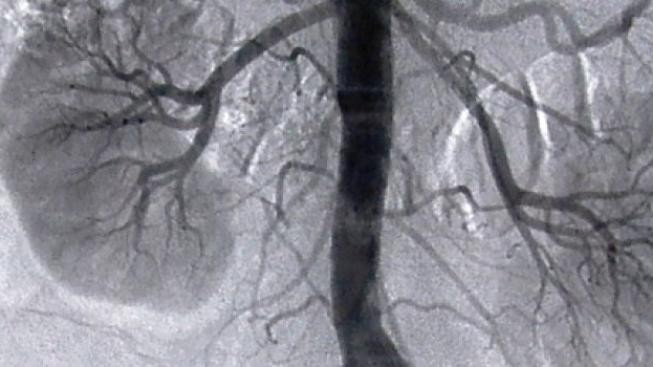

První úspěšnou transplantaci ledviny člověku provedl americký chirurg Richard Lawler před 60 lety, 17. června 1950, v chicagské nemocnici. Během pouhých 45 minut voperoval Ruth Tuckerové ledvinu mrtvé ženy.

Za měsíc byla pacientka propuštěna do domácího ošetřování. V dubnu 1951 se ale musela do nemocnice vrátit, protože její ledvina produkovala stále méně moči. Při nové operaci Lawler objevil mrtvou tkáň, která znamenala odmítnutí implantátu organismem. Přesto první pacientka s transplantovanou ledvinou žila dalších pět let.

První úspěšnou transplantaci ledviny mezi jednovaječnými dvojčaty provedli bostonští specialisté Joseph Murray a John Merrill v prosinci 1954, první transplantaci mezi geneticky odlišnými jedinci provedl Joseph Murray v lednu 1959 a v roce 1962 byla provedena první transplantace mezi nepříbuznými dárci. Některé prameny uvádějí, že vůbec první transplantaci ledviny provedl v roce 1936 ruský lékař Sergej Voronov, pacientka ale po dvou dnech zemřela.

První transplantace ledviny v Československu byla provedena 23. listopadu 1961 ve Fakultní nemocnici v Hradci Králové, pacientka ale zemřela po 16 dnech na infekci. První úspěšná transplantace ledviny, po které žil pacient s transplantovaným orgánem tři roky, se v Československu uskutečnila v Institutu klinické a experimentální medicíny (IKEM) 21. března 1966.